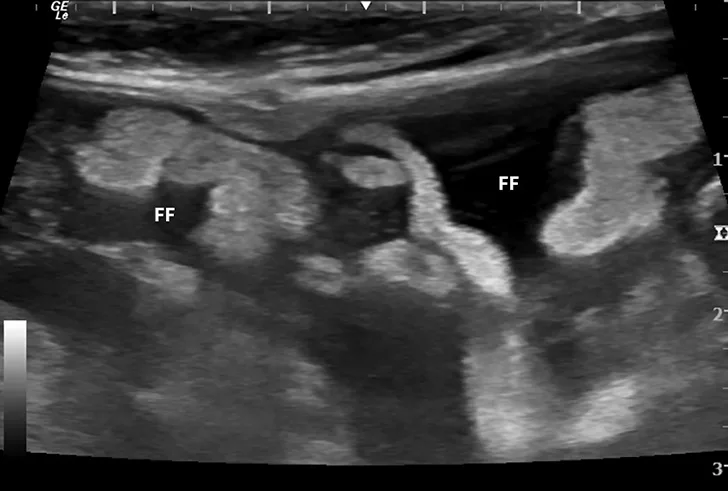

Abdominal ultrasound images from a cat.

FIGURE 1

Ultrasound image showing abdominal effusion in a cat with wet FIP. Anechoic fluid is present between organs, distending the abdomen. FF = free fluid; L = liver; S = spleen; K = kidney